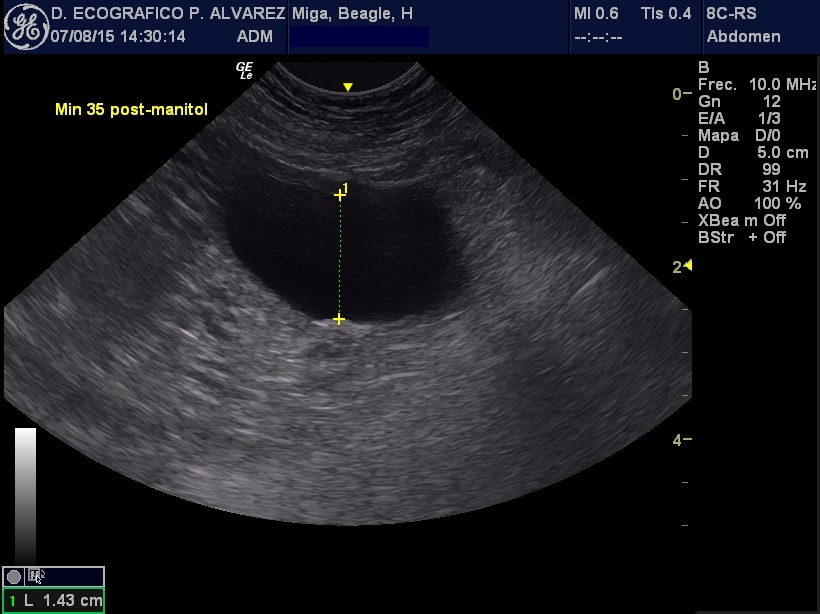

Se procede entonces a realizar un protocolo de diuresis forzada, inicialmente con furosemida (dos dosis) y posteriormente con manitol en CRI, valorándose la producción de orina a lo largo del tiempo midiendo el grosor de la luz vesical tomando el mismo corte ecográfico a igual profundidad y aumento.

Pese a todos los esfuerzos, la producción de orina es nula y el cuadro convulsivo no se controla, por lo que se decide practicar la eutanasia a Miga.